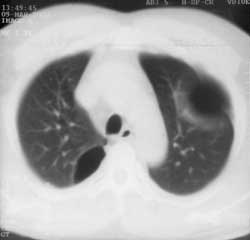

Рис. 3. В правом реберно-позвоночном углу булла, не выявленная на обычной рентгенограмме.